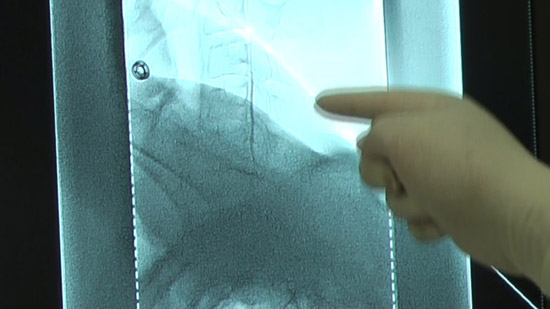

(4)Conduct an epidural puncture by the resistance loss method, checking with the image on the radioscopy screen.

※Inject the contrast medium and check it again. Capture a confirmation image at the same time.

(5)Connect an extension tube to the puncture needle and fill the autologous blood syringe with the collected blood (mixture contrast medium).

Check with the image on the radioscopy screen.

Check subjective physical condition of patients after 10 cc infusion and capture a projectional image.

Capture projectional images at the end of infusion.